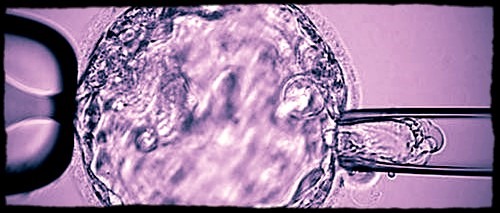

Biopsy procedure of a blastocyst (day-5 embryo) for subsequent preimplantation genetic testing